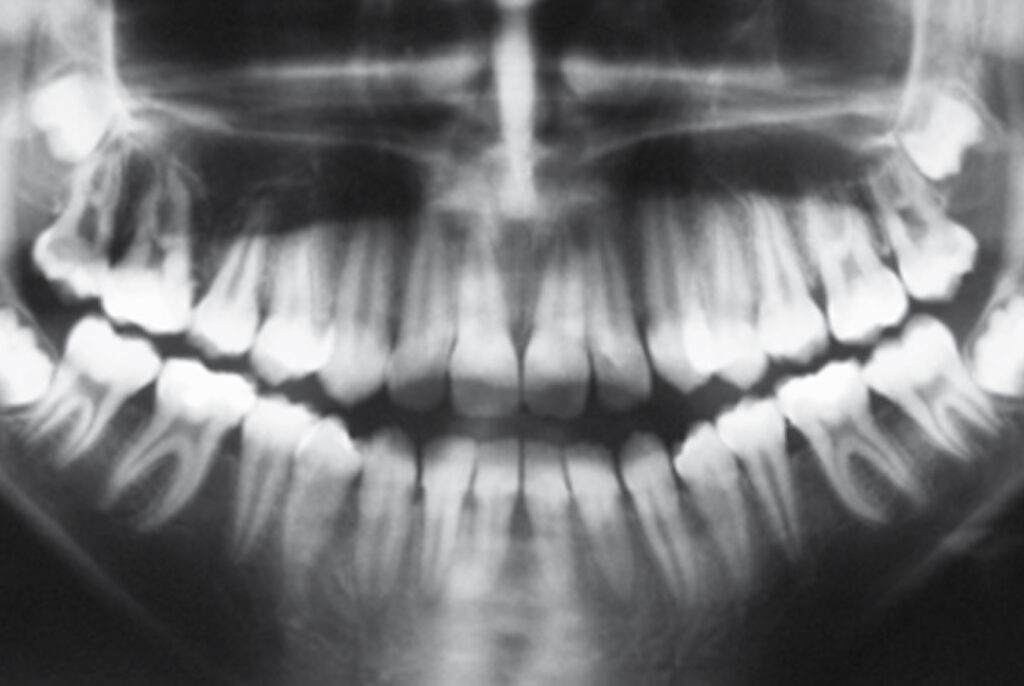

Na radiografia panorâmica, pode-se perceber a presença de todos os dentes, inclusive dos germes dos terceiros molares (Figura 3).